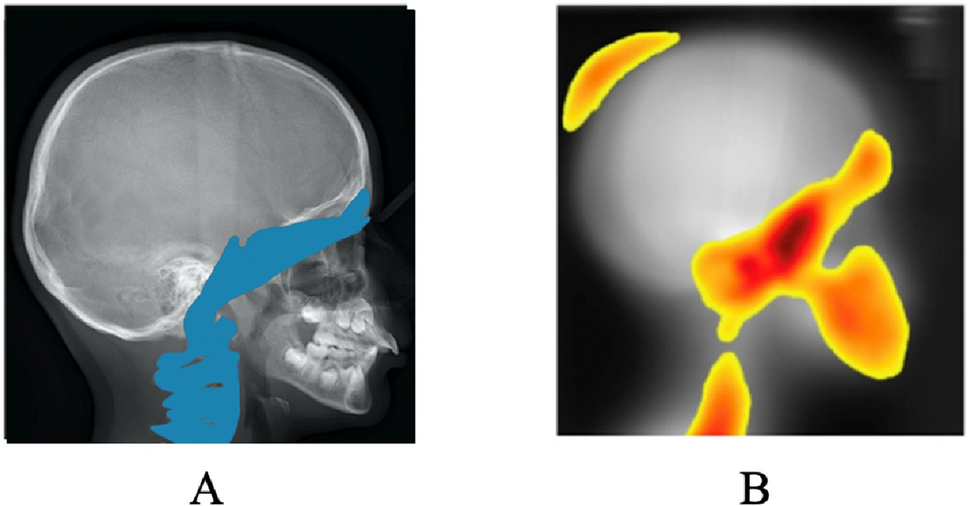

Figure 4

Craniofacial areas: (A) Anatomical structure identified in literature as being impacted by mandibular retrognathia: the frontal sinus, the base of the skull, the sphenoid and the cervical vertebrae; (B) Anatomical structure highlighted by our global activation map according to MIE-ICNN: the structures already identified in litterature, as well as the parietal bone.